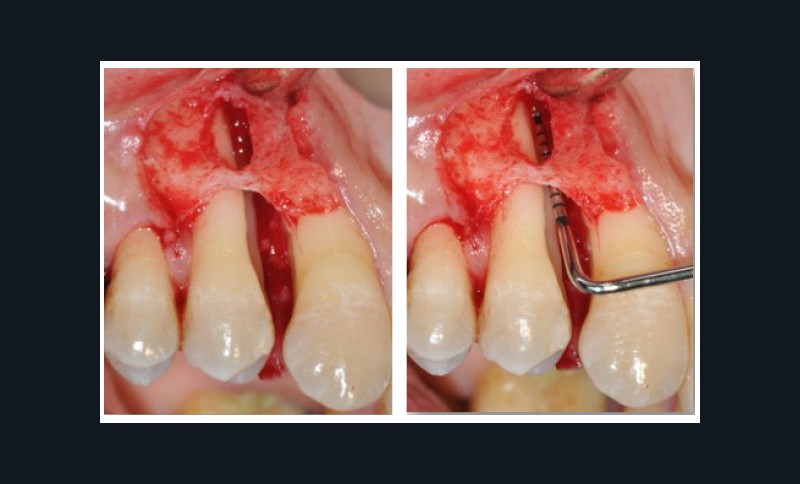

Les instruments manuels sont limités aux curettes de Gracey et les instruments ultrasonores aux micro-inserts (fig. 2a et b). Seules leurs formes et tailles réduites permettent de pénétrer au fond des poches. Les avantages et inconvénients seront discutés. Le choix du débridement ultrasonique répond aux objectifs du contrôle de l’infection par la désorganisation et l’élimination des biofilms. La stratégie et l’organisation proposées peuvent s’adapter aussi bien dans le traitement initial que dans le suivi tout au long de la vie du patient. Si le traitement étiologique est toujours nécessaire, il peut être insuffisant en fonction des objectifs de traitement ; c’est un préalable aux techniques chirurgicales.

Quand et comment intervenir par voie chirurgicale ? C’est la question à laquelle Filippo Graziani tentera de répondre car, si les techniques de débridement non chirurgical ont permis de repousser les limites des indications chirurgicales, celles-ci sont encore nécessaires (fig. 3a et b). Le choix chirurgical dépend à la fois des objectifs définis initialement avec le patient et des résultats du traitement étiologique. Les séances de chirurgie peuvent être généralisées ou localisées, et faire appel aux différentes techniques d’assainissement, de résection ou d’addition, avec la possibilité de régénération tissulaire par apport de biomatériaux.